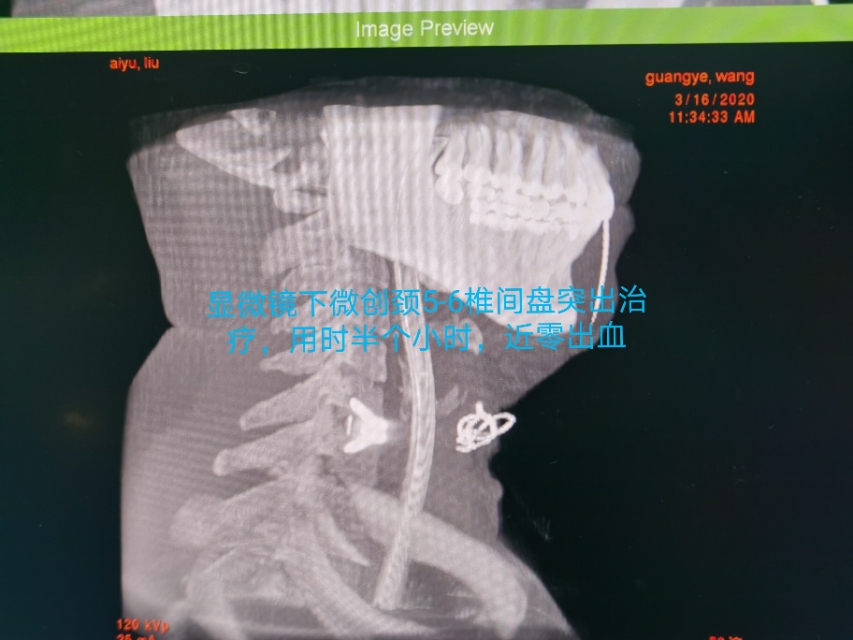

中年人疫情期居家长期卧床及长期看电脑手机,颈椎病复发今天显微镜下微创治疗,颈6-7巨大椎间盘突出.压迫神经根管,伴左上肢剧烈放射痛,显微镜下微创颈椎间盘突出治疗,用时半个小时,近零出血,取出压迫神经4块髓核,切除后纵韧带,减压至脊髓表面,脊髓恢复正常搏动,神经监护神经功能恢复好